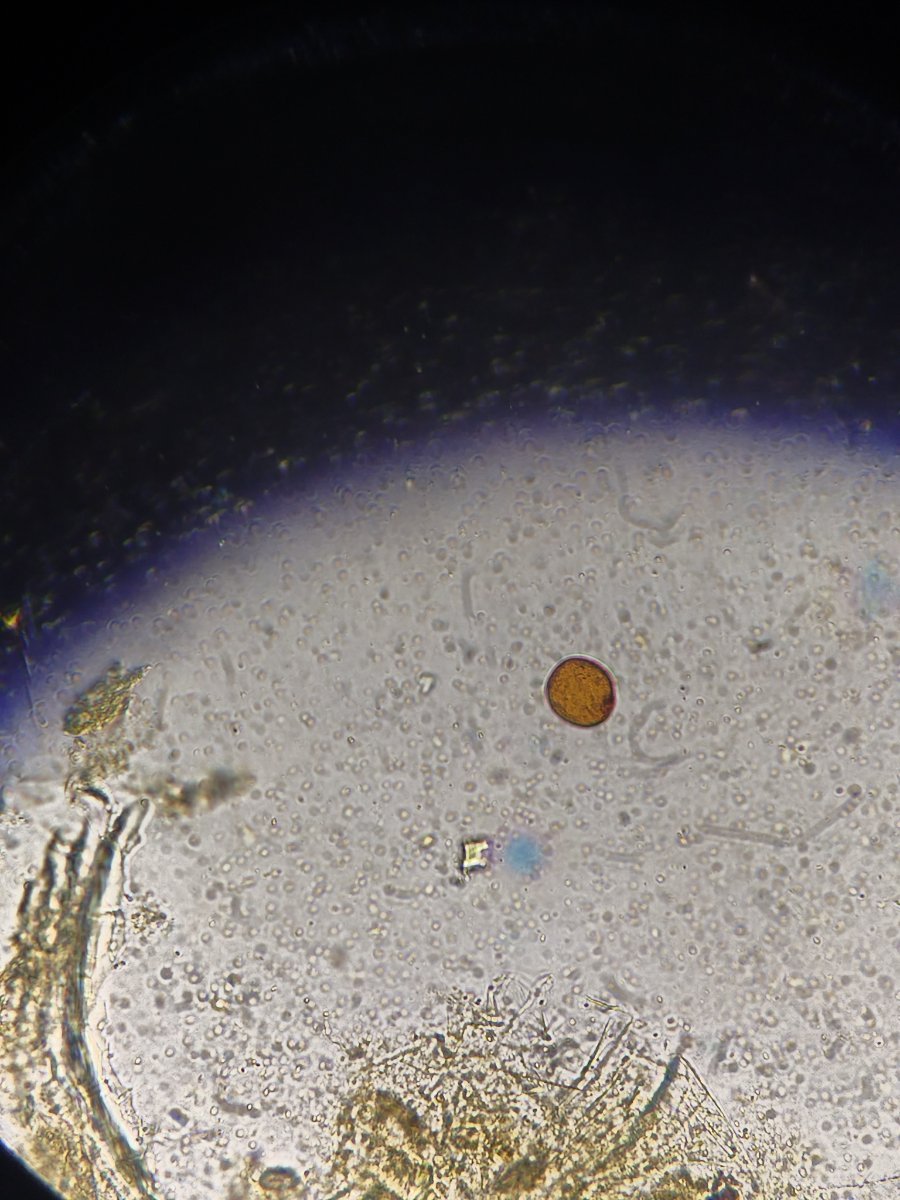

Здравствуйте. Помогите, пожалуйста, разобраться. Волнистый попугай, девочка, 3 года 5 месяцев. Лечили мегабактериоз, на вчерашней микроскопии ни одной мегабактерии, однако рвота и непереваренные зерна в помете остаются. Сделали рентген, орнитологи в замешательстве, у каждого свое отличное мнение по поводу преджелудка , печени и новообразовании в лёгких. В помете также нашли много пыльцы, однако возможно , что это глисты. Снова не понятно. Помогите , пожалуйста, разобраться с рентгеном и микроскопией. Фото прикладываю.